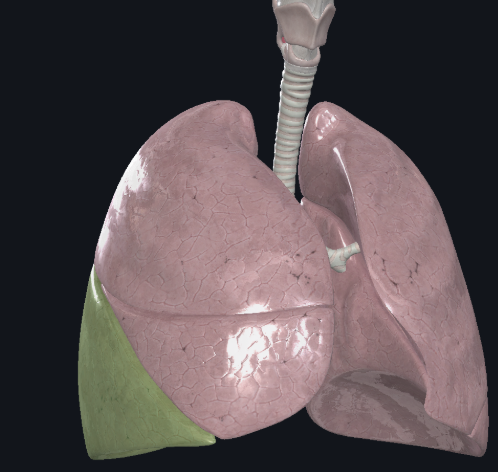

Inferior lobe of the right lung

What structure is this?

Oblique fissure of right lung

What structure is this?